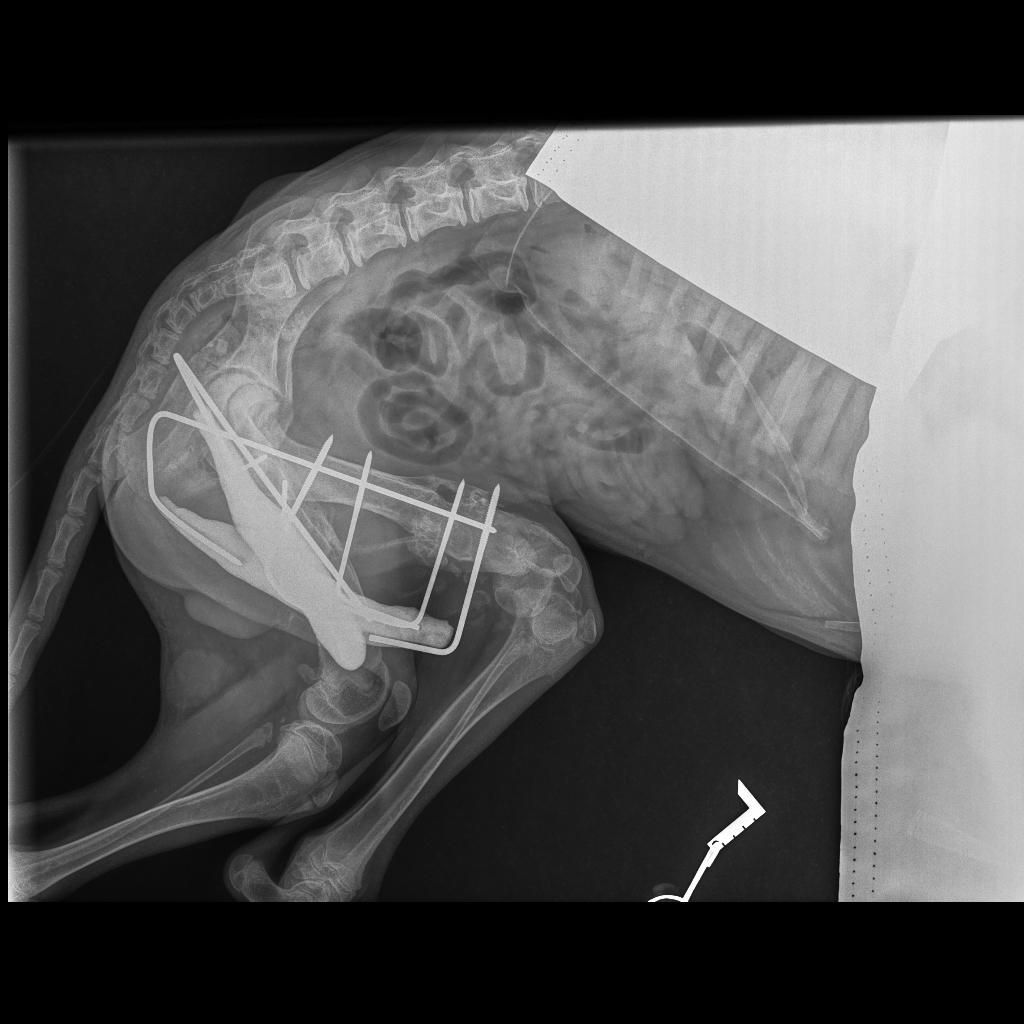

Erste Operation gelungen!

Am 16.11. ist Cosima Senta operiert worden, zuerst ist der linke Kopf des Hüftgelenksknochens entfernt bzw. Der Knochen gerichtet worden und so die Fehlstellung der Beine korrigiert worden. Beide Seiten sind leider betroffen, aber links musste zuerst behandelt werden. Zugleich wurden die Schwanzwirbel so gerichtet, dass der Knochenbau gerichtet ist, damit die Hündin einmal wieder korrekt und schmerzfrei laufen kann. Zugleich mussten die Milchdrüsen im betroffenen Bereich entfernt werden.

Diese erste Operation hat 600 € gekostet und wir danken von Herzen Lissy Schleich, die das Geld für Cosima Senta gespendet hat.

Der Tierarzt empfiehlt jetzt ein CT, um nach diesem ersten Schritt weiter planen zu können, welche Knochenschnitte und Stabilisierungen nötig sind, wie ein Neuaufbau im Beckenbereich durch Treiber gestützt sinnvoll ist. Allein für das CT müssen wir weitere 300 € stemmen, hinzukommen pro Seite 300 € für die Drei-D-Stabilisatoren/ die Treiber bzw 550 € für beide zusammen, wenn sie zeitgleich fixiert werden sollen, worüber die CT Aufnahme aufklären wird. Für uns bedeutet dies, wir sammeln weiter, damit Cosima Senta bald unbeschwert laufen und springen kann. Sie hat es wirklich verdient. Hilfe ist hier gefordert, diese knapp 900 € müssen wir erst einmal zusammenbringen. Jede Spende für die arme Maus hilft, sie hat doch noch ein ganzes Leben vor sich.